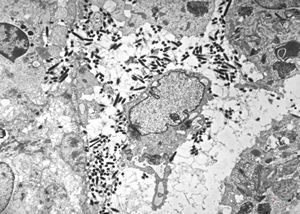

Whipple disease